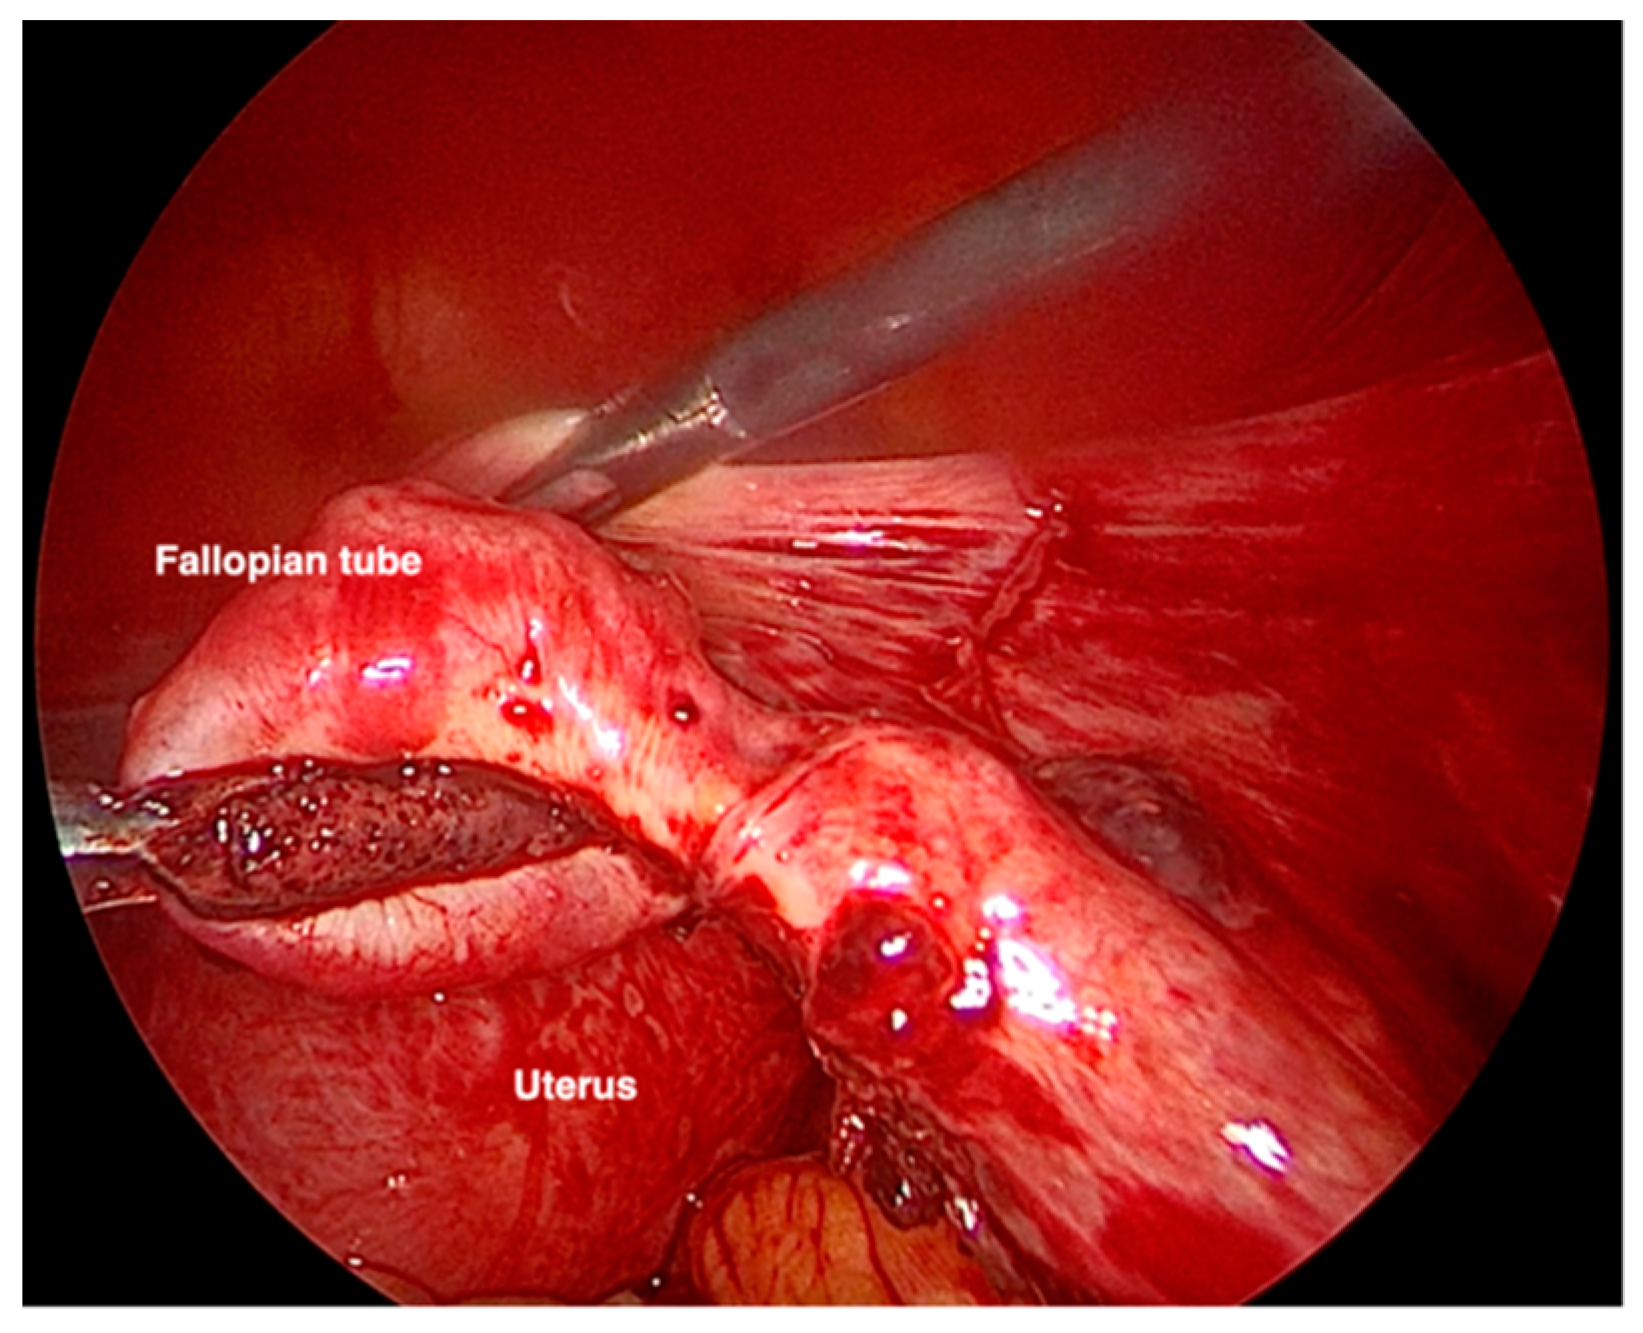

When she came to our institution, her vital signs were stable. She showed no sign or symptoms of rupture of the ectopic pregnancy. Blood samples were in range, and there were no signs of shock. The physical examination revealed a soft abdomen with no tenderness or rigidity. The ultrasound examination demonstrated a gestational sac in the right tubal area, containing an embryo of 10 + 4 weeks’ (Crown Rump Length of 36.7 mm) (Figure 1). Fetal heartbeat was present. No intrauterine pregnancy was noted. There was a 35 mm layer of free fluid in the pouch of Douglas. Since the diagnosis was already evident, the beta-HCG levels were not measured.

Figure 1. Ultrasound examination demonstrating a 10 + 4 weeks’ tubal pregnancy with a fetal heartbeat.